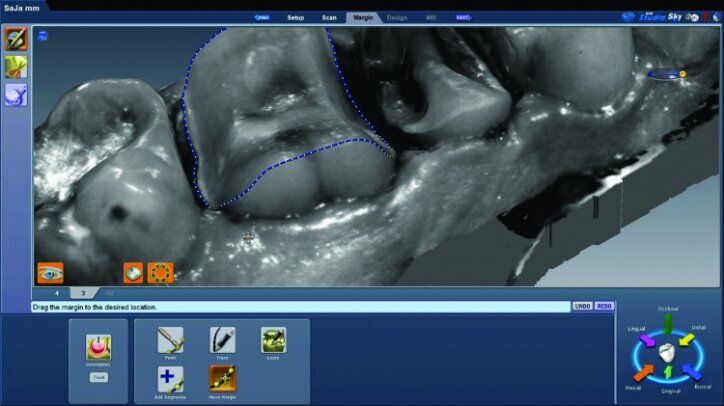

The preparation model was examined in data density view to verify adequate data was obtained during the scanning of the preparations (Fig. 26c).

Any areas lacking adequate data were scanned further until adequate data was obtained. Next, orientation of the preparation model was performed (Fig. 26d). Orientation is for optimal design, not path of insertion. The margins were then traced and viewed in ICE mode, which provides a rendering of the scanned images for a clear view of the margins, teeth and tissues (Figs. 26e, f).

The initial proposals for the restorations were made using Library A and autogenesis, which is morphogenesis of the library tooth with the neighbouring teeth (Figs. 26g–i).